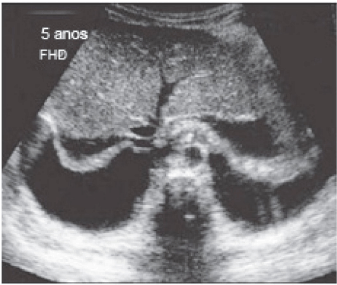

A febre do dengue hemorrágico (FDH) é uma arbovirose responsável por epidemias anuais no Brasil. Sua principal característica é o aumento da permeabilidade capilar, representada pela fuga de líquido e albumina para o espaço extravascular, levando a derrames cavitários e hemoconcentração com elevação do hematócrito, descrita como polisserosite, classificada em formas leves e graves, segundo critérios da Organização Mundial da Saúde. Embora os achados à ultrassonografia sejam inespecíficos, o método contribui para o diagnóstico precoce em pacientes com FHD e no diagnóstico diferencial de outras doenças febris.

Considerando as informações abaixo, assinale a alternativa correta quanto à principal hipótese diagnóstica da imagem ultrassonográfica apresentada.